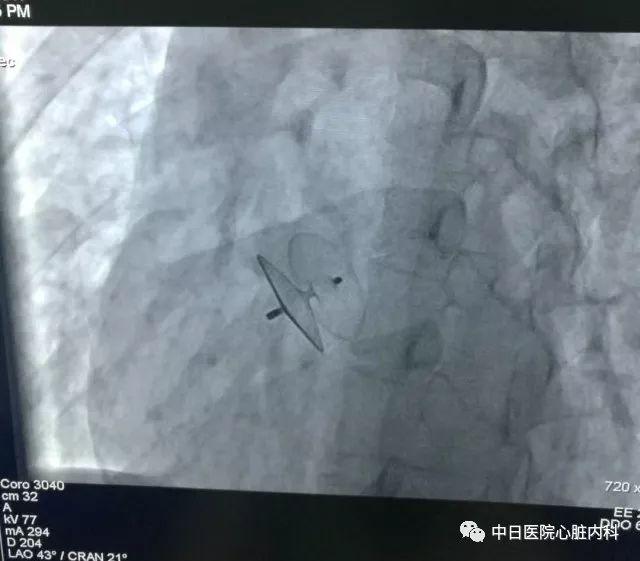

实际手术后透视效果图

卵圆孔未闭不仅与脑梗塞关系密切,它也是一部分偏头痛的罪魁祸首。介入封堵治疗,是目前治疗卵圆孔未闭的主要手段。这是一种微创的操作,是在局部麻醉下,穿刺一侧股静脉,经直径3mm的导管,把一个封堵伞释放于未闭合的卵圆孔处,阻断血栓、气栓以及静脉系统特殊物质向动脉系统分流的通道,从而对符合指征的患者,起到预防脑梗、减轻偏头痛的作用。